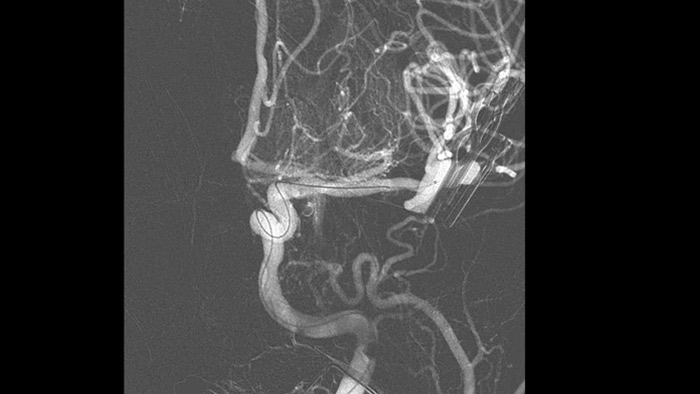

Visualice anatomías patológicas tortuosas en 3D de alta fidelidad

SmartCT Angio

SmartCT Angio proporciona una vista volumétrica en unos segundos para ayudar a evaluar la ubicación, el tamaño, el diámetro y grosor del cuello y la gravedad del aneurisma para la planificación del tratamiento. Los volúmenes 3D se visualizan con alta resolución espacial y compensación automática del movimiento del paciente.